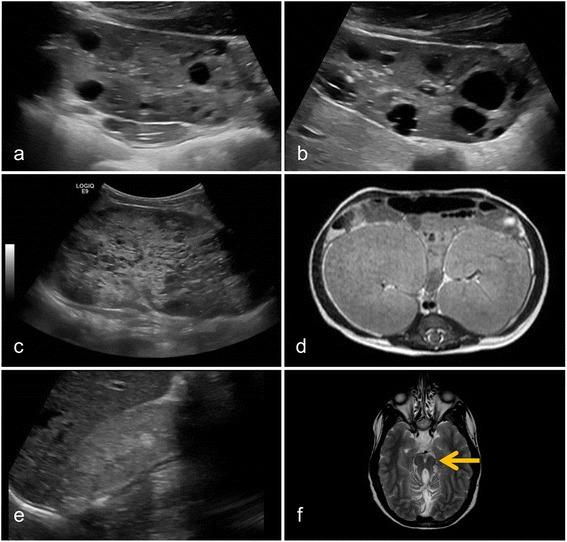

Cilia are nowadays considered to be crucial cellular structures controlling diverse intracellular signaling cascades. Dysfunction of cilia leads to a pleiotropic group of diseases ranging from cystic kidney disease via neurologic disorders to metabolic phenotypes and cardiac malformations. According to the underlying cellular pathophysiology, these diverse disorders have been subsumed under the term "ciliopathies".

如今,纤毛被认为是控制多种细胞内信号级联反应的关键细胞结构。纤毛功能障碍会导致一系列多效性疾病,从多囊肾病到神经系统疾病,再到代谢表型和心脏畸形。根据潜在的细胞病理生理学,这些不同的疾病被归为“纤毛病”这一术语之下。